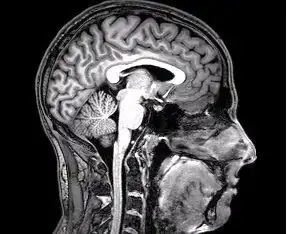

Imagen estructural y funcional

Hay varios métodos para detectar los cambios de actividad cerebral mediante imágenes tridimensionales de los cambios locales en el flujo sanguíneo cerebral. Los antiguos métodos son la SPECT y la PET, que dependen de la inyección de marcadores radiactivos en el torrente sanguíneo.

La imagen por resonancia magnética funcional (IRMf), tiene considerablemente mejor resolución espacial y no implica ninguna radiactividad.[25] La IRMf puede localizar los cambios de actividad cerebral en regiones tan pequeñas como 1 mm³ (milímetro cúbico).

El inconveniente es que la resolución temporal es pobre: cuando aumenta la actividad cerebral, el flujo sanguíneo responde con un retraso de 1 a 5 s (segundos) y tiene una duración de al menos 10 s. Por lo tanto, la IRMf es una herramienta muy útil para saber cuales regiones del cerebro están involucradas en una determinada conducta, pero da poca información sobre la dinámica temporal de sus respuestas. Una ventaja importante de la IRMf es que, debido a que no es invasiva, puede ser fácilmente utilizada en seres humanos.